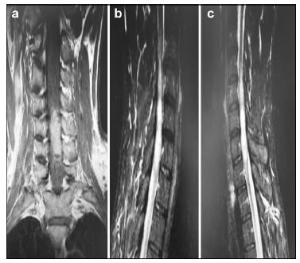

20170512093634  Figure 1 a–c. Preoperative MR images of Case 1.